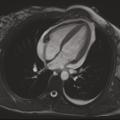

L’imagerie par résonance magnétique (IRM) cardiaque (fig. 2) confirme l’inflammation du péricarde, ce dernier étant épaissi et brillant en T2 et rehaussé après injection de gadolinium, et permet de rechercher une myocardite associée. Les biopsies péricardiques sont réservées aux tamponnades récidivantes, aux suspicions de péricardite bactérienne ou néoplasique, et aux cas de péricardites s’aggravant sous traitement sans cause définie.